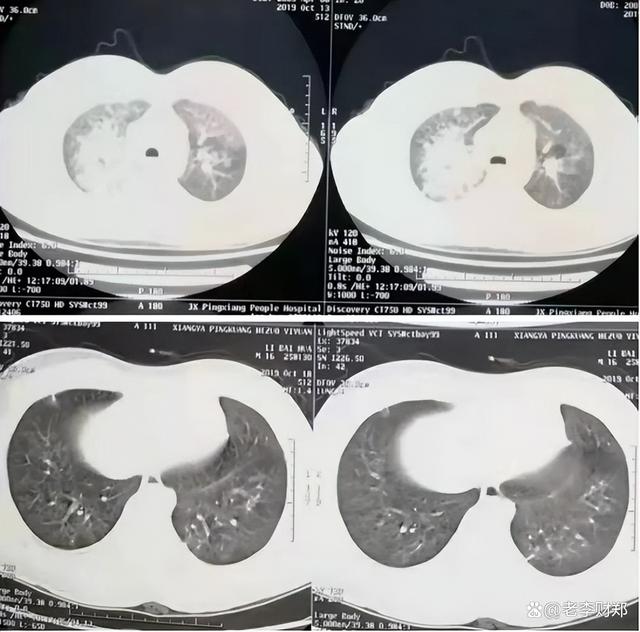

除此之外,还有大量的存在基础病的病人,在感染新冠之后导致自身病情病变甚至是加重,从而需要入院进行治疗,而且大量新冠患者存在白肺现象,从而占用了大量的医用资源,导致医疗资源吃紧。